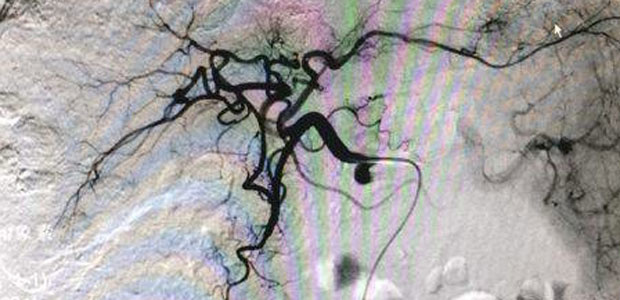

On 10th, April 2017, microcatheter superselection was applied to a male patient who suffered primary liver cancer with multiple hepatic metastases. After an embolism with lipiodol a...[Detail]